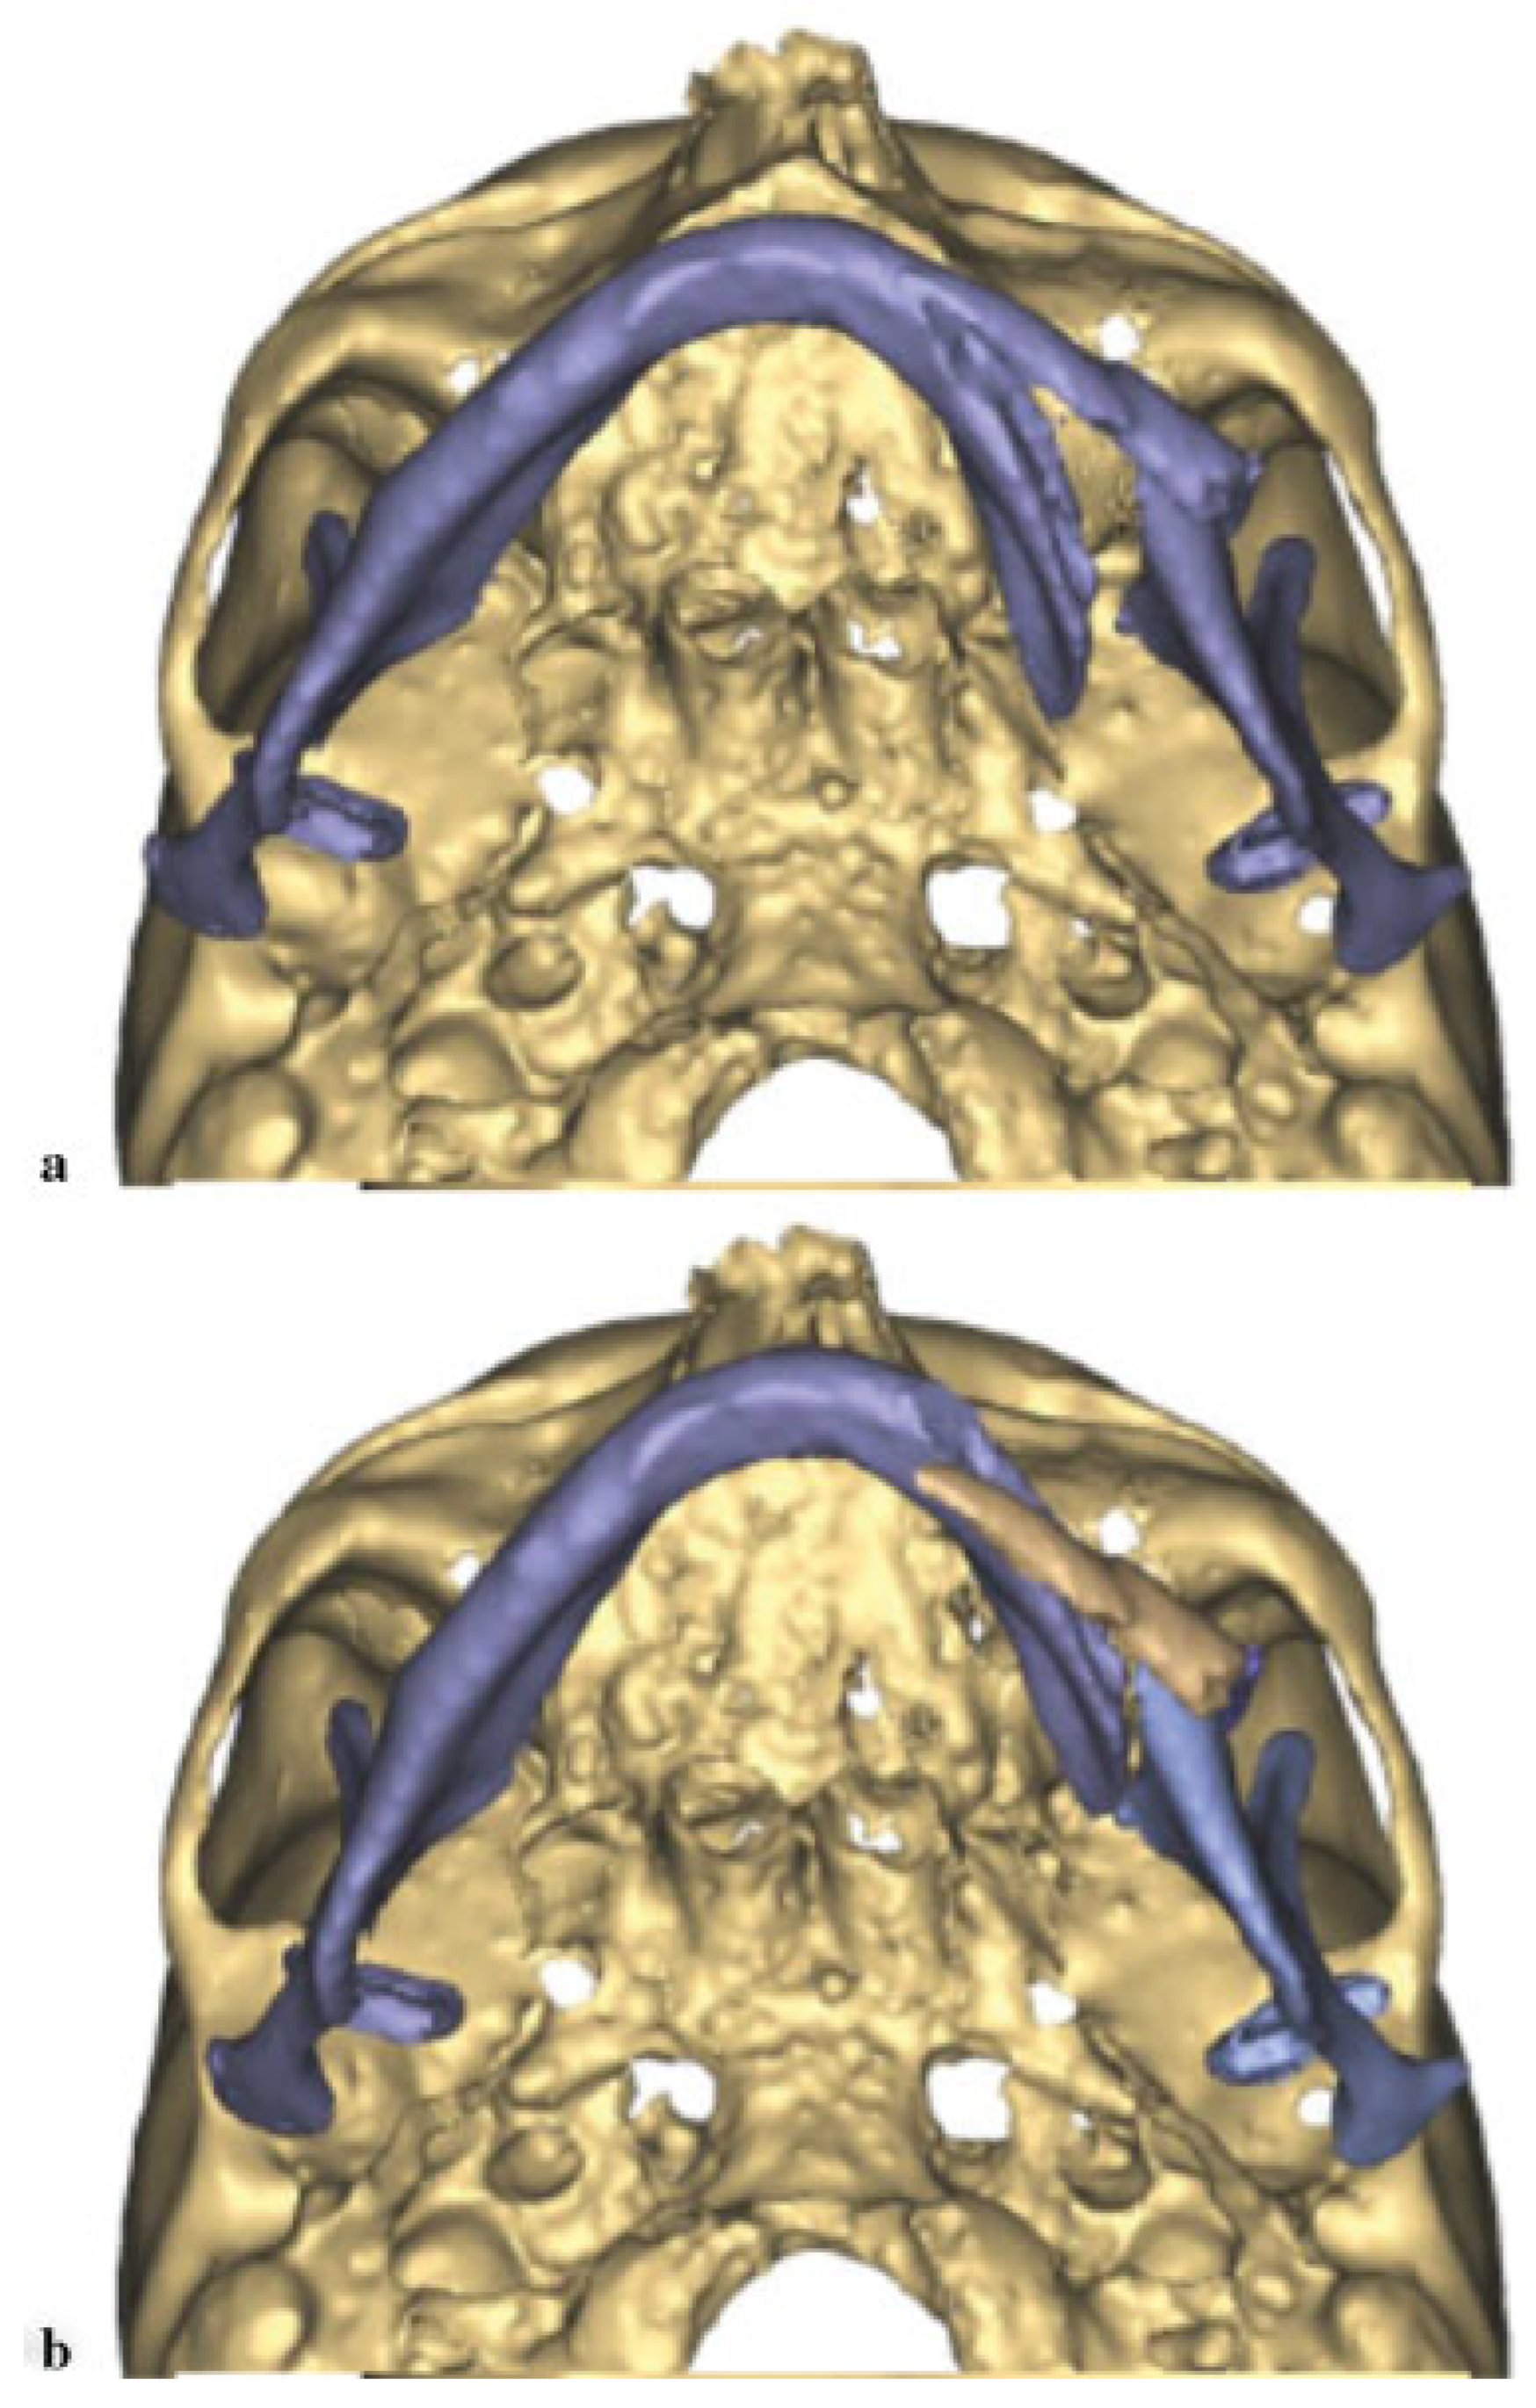

A 70-year-old female patient presented as an outpatient for definitive treatment of her pathologic mandibular fracture, orocutaneous fistula, and chronic osteomyelitis. Clinically, she had a draining orocutaneous fistula in the submental region which communicated intraorally at the left lingual border of the mandible. The left mandibular body was mobile and her chin was deviated 2 cm to the left. She had a severely atrophied mandible in the area of the fracture with poor remaining dentition. A cone beam computed tomography (CBCT) was obtained. The approximate defect was measured at 4 to 5 cm in the left body (Figure 6).

Prior to surgery, VSP was implemented to plan the procedure (Materialize, Plymouth, MI). A CBCT was obtained. Similar to the previous case, the midline of the major segment was aligned with the midline of the maxilla (Figure 7a,b). The displaced smaller segment was placed in the glenoid fossa and the inferior borders were aligned. A mirror image of the unaffected right side of the mandible was then superimposed. The area of lytic bone was outlined and a model was fabricated. A 2.5-mm locking reconstruction plate was prebent according to the 3D model using the mirror image model with enough length to span the area that would be reconstructed (Figure 8).

Figure 6. Pathologic fracture with displacement of the minor segment.

Figure 7. (a) Displacement of the jaw prior to manipulation. (b) Alignment of the midline of the mandible with the maxilla revealing the large defect on the jaw lateral border.